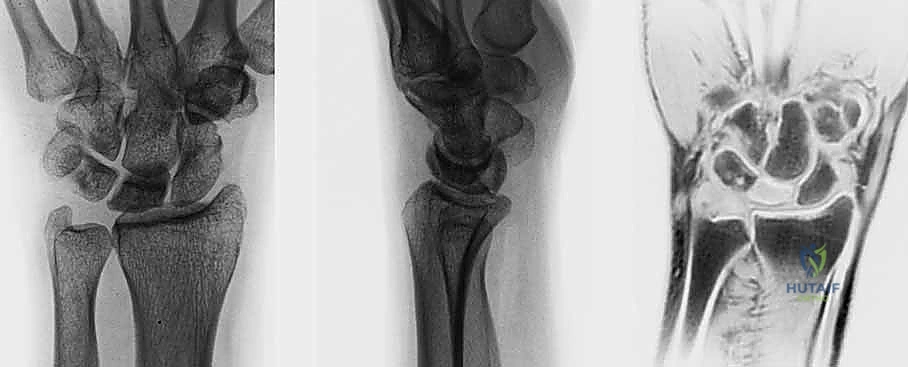

- الأشعة السينية (X-rays): هي الخطوة الأولى. في المراحل المبكرة جداً، قد تظهر الأشعة السينية طبيعية تماماً. في المراحل اللاحقة، يظهر العظم الهلالي بلون أبيض ناصع (متصلب)، ثم يبدأ في الظهور مفلطحاً أو متفتتاً.

- التصوير بالرنين المغناطيسي (MRI): هو المعيار الذهبي للتشخيص المبكر. يمكن للرنين المغناطيسي اكتشاف نقص التروية الدموية (وذمة العظم) قبل أشهر من ظهور أي تغيرات في الأشعة السينية. يعتمد الدكتور هطيف بشكل كبير على الرنين المغناطيسي لتحديد مرحلة المرض بدقة.

- التصوير المقطعي المحوسب (CT Scan): يُستخدم لتقييم مدى تفتت العظم الهلالي وبنيته ثلاثية الأبعاد، وهو أمر حاسم في التخطيط الجراحي.

مراحل ليختمان (Lichtman Classification) لمرض كينبوك

يُصنف المرض عالمياً باستخدام نظام ليختمان، وهو دليل أساسي يحدد مسار العلاج:

| المرحلة | الوصف الطبي والشعاعي | العلاج المقترح عادةً |

|---|---|---|

| المرحلة الأولى (Stage I) | أشعة سينية طبيعية. ألم خفيف. الرنين المغناطيسي يظهر نقص التروية. العظم محتفظ بشكله. | علاج تحفظي (تثبيت) أو تدخل جراحي بسيط لتحسين التروية. |

| المرحلة الثانية (Stage II) | الأشعة السينية تظهر العظم الهلالي أكثر بياضاً (تصلب). العظم لا يزال محتفظاً بشكله العام ولكن قد تظهر خطوط كسر دقيقة. | جراحة لتفريغ الضغط أو زراعة طعم وعائي. |

| المرحلة الثالثة أ (Stage IIIA) | انهيار وتفلطح العظم الهلالي. تفتت الأجزاء. لا يوجد انهيار في ارتفاع عظام الرسغ الكلية. | زراعة طعم عظمي وعائي + جراحة تسوية المفصل (تقصير العظم الكبير أو تطويل الكعبرة). |

| المرحلة الثالثة ب (Stage IIIB) | انهيار العظم الهلالي مع انهيار ارتفاع الرسغ وانحراف العظم الزورقي. ميكانيكا الرسغ مضطربة. | دمج جزئي لعظام الرسغ (Partial Wrist Arthrodesis) أو استئصال الصف القريب. |

| المرحلة الرابعة (Stage IV) | انهيار كامل للرسغ مع تطور خشونة متقدمة (التهاب مفاصل) في المفاصل المجاورة. | دمج كلي للرسغ (Total Wrist Arthrodesis) أو استبدال المفصل. |